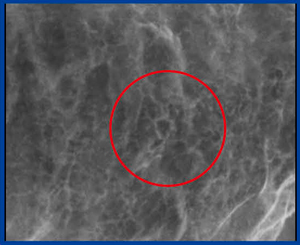

X線画像(図4)では,小さな顆粒と周囲の棘状の変化があり,びらんではないことがわかる。しかし,これを見つけるのは容易ではなく,画像精度は向上したものの,診断には熟練を要することが今後の課題である。

図4 微小胃がん(4mm×3mm,未分化型)の |